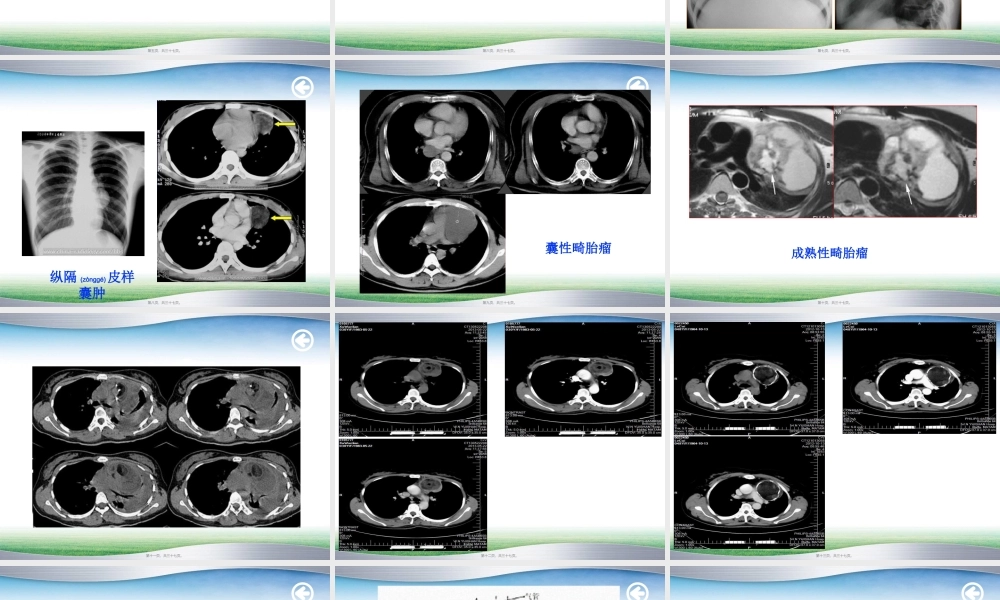

畸胎瘤09影像(yǐnɡxiànɡ)沈菲第一页,共三十七页。纵隔是左右纵膈胸膜及其间所夹的器官和组织纵隔是左右纵膈胸膜及其间所夹的器官和组织的总称,位于胸腔中部,其前界是胸骨,后面的总称,位于胸腔中部,其前界是胸骨,后面是脊柱,两侧为纵隔胸膜。向上与颈部相连,是脊柱,两侧为纵隔胸膜。向上与颈部相连,向下延伸至膈肌。向下延伸至膈肌。解剖学通常采用四分法:解剖学通常采用四分法:即以胸骨角和第即以胸骨角和第44胸椎体的下缘的平胸椎体的下缘的平面将纵膈分为面将纵膈分为(fēnwéi)(fēnwéi)上纵隔和下纵隔;下纵上纵隔和下纵隔;下纵膈又以心包的前后壁为界,分为膈又以心包的前后壁为界,分为(fēnwéi)(fēnwéi)前纵前纵隔、中纵隔和后纵隔。隔、中纵隔和后纵隔。第二页,共三十七页。【定义】由种质细胞或胚胎干细胞衍生而来的瘤性组织,排列结构错乱,往往含有外、中、内三个胚层的多种组织成分。纵膈畸胎瘤是发生在纵膈的生殖细胞肿瘤,一般认为畸胎瘤多系个体发育初期,部分多能性原始细胞迷离出来,在纵隔内增殖发展成肿瘤。绝大多数位于前纵隔,多发于30岁以下的青壮年,男女发病率无明显差异。良性畸胎瘤多见,病程较长。早期肿瘤体积较小,可无任何症状,随着体积增大出现压迫症状、继发感染和恶变、或侵入周围组织,产生相应的临床表现。手术治疗是首选(shǒuxuǎn),效果良好。第三页,共三十七页。【病理生理】根据畸胎瘤成熟程度分为3类:囊性成熟性畸胎瘤:又称皮样囊肿,包膜完整,腔内可含有毛发、皮脂、软骨成分,恶变者约9%~15%,其中以鳞癌最常见,腺癌少见(shǎojiàn)。实性畸胎瘤:呈实性团块状,切面有大小不等的囊腔,内有出血和坏死,镜下可见所有胚层组织的成分,以内胚层成分居多。此病的成熟程度介于良、恶性之间者为中间型畸胎瘤。未成熟型畸胎瘤:瘤内含有未分化的幼稚组织成分,又称恶性畸胎瘤。生长迅速,常浸润邻近组织而引起严重症状,经血和淋巴转移,通常以腺癌多见。第四页,共三十七页。【临床表现】无痛性肿块:这是畸胎瘤最常见的症状,多为圆形囊性、边界清楚、质地软硬不匀,甚至可扪及骨性结节。压迫和腔道梗阻症状:纵隔畸胎瘤常可压迫呼吸道而引起呛咳、呼吸困难及颈静脉怒张。急性症状:畸胎瘤当发生继发感染和囊内出血时,常可肿块迅速增大,局部明显(míngxiǎn)压痛,并同时伴有发热、贫血、休克等全身感染或失血症状。肿瘤恶变的症状:恶性畸胎瘤和良性畸...